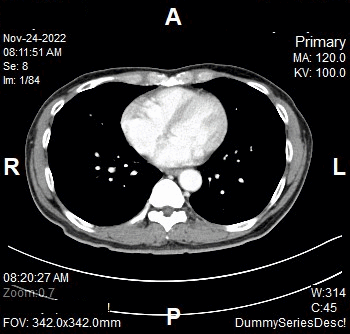

Scanning Parameters

- kV: 100 kV

- mAs: Tube Current Modulation (TCM)

- Scanning Direction: Craniocaudal

- Scan Delay: 4 s

- Slice: 5.0mm

- Image Comment: Non Contrast

- Pitch: 0.6

- Quality Reference mAs : 230